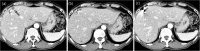

Objective: Stereotactic body radiation therapy (SBRT) for the treatment of a malignancy in the liver requires the perilesional implantation of fiducial markers for lesion detection. The purpose of this study is to evaluate the efficacy and safety of ultrasound (US) -guided marker implantation for SBRT.

Methods: We retrospectively reviewed 299, US-guided, intrahepatic fiducial markers implanted in 101 patients between November 2013 and September 2014. SBRT-planning CT images were analyzed to determine the technical success of the implantation, the mean distance between the tumor margin and the marker, with the ideal location of fiducials defined as the distance between a marker and a tumor less than 3 cm and the distance between markers greater than 2 cm according to the tumor conspicuity seen on gray-scale US and the artifact obscuring tumor margins. We also evaluated procedure-related major and minor complications.

Results: Technical success was achieved in 291 (97.3%) fiducial marker implantations. The mean distance between the tumor and the marker was 3.1 cm (S.D., 2.1 cm; range, 0-9.5 cm). Of 101 patients, 72 lesions (71.3%, 2.2 ± 1.0 cm; range, 0-3.0 cm) had fiducial markers located in an ideal location. The ideal location of fiducials was more common in visible lesions than in poorly conspicuous lesions (90.2% vs. 52.0%, P < 0.001). Seventeen markers (5.8%) developed beam-hardening artifacts obscuring the tumor margins. There were no major complications, although 12 patients (11.9%) developed minor complications.